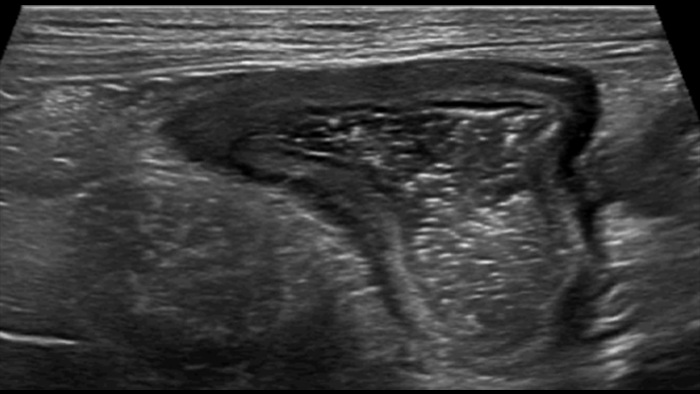

Dans le cas de la rectocolite hémorragique, en présence d’une forme grave et aiguë, la paroi est parfois plus épaisse. Ici, l’épaisseur des couches sous-muqueuse et muqueuse est augmentée en raison d’un œdème, tandis que la couche musculaire reste normale. En cas de forme chronique tardive, des pseudopolypes sont visibles à l’intérieur du lumen, ce qui n’a jamais été décrit à ma connaissance.

Late form pseudopolyps